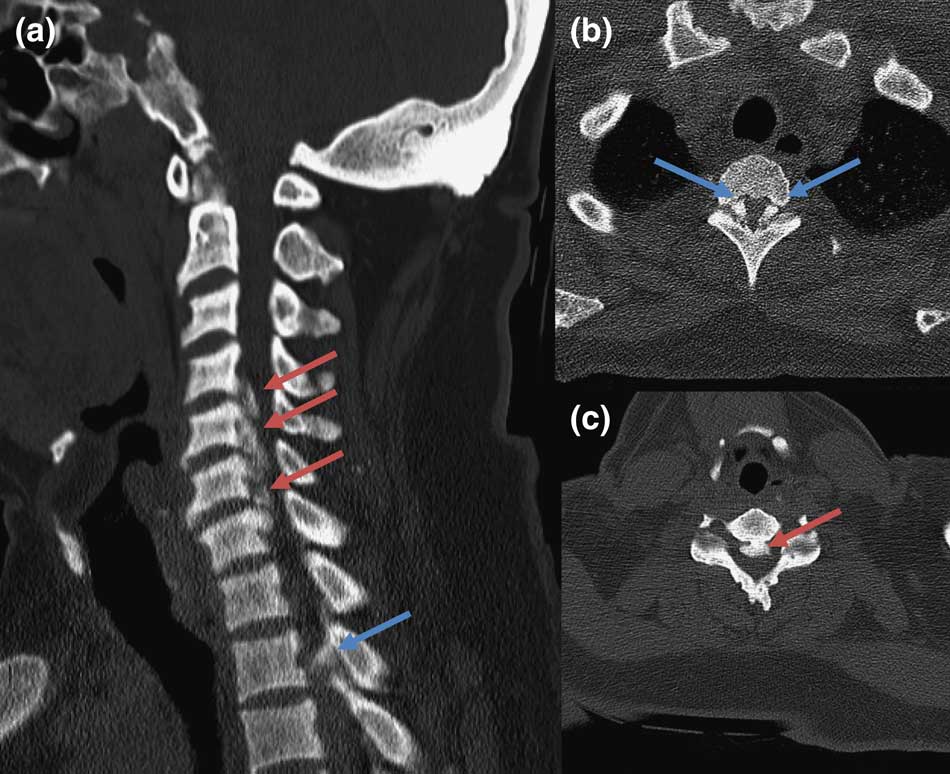

Figure 1 CT cervical spine, sagittal (A) and axial (B, C): marked ossification of posterior longitudinal ligament (red arrows) and ligamentum flavum (blue arrows), causing severe central canal stenosis.

A 45-year-old Caucasian man with X-linked hypophosphataemic rickets (XLHR), and no other risk factors for ossification of the posterior longitudinal ligament (OPLL), presented with a 3-week history of progressive right hand and leg weakness. This was noticed when weight-bearing, 5 weeks after a right total knee replacement. Examination revealed right upper limb and right lower limb weakness and bilateral lower limb spasticity with extensor plantar responses, compatible with a cervical myelopathy. CT cervical spine revealed coarse calcification of the posterior longitudinal ligaments (PLL), from C4 to C7, and of the ligamentum flavum (LF), from T3 to T4, causing severe central canal stenosis (Figure 1). MRI spine showed extensive abnormal ossification of the PLL at C2-C6, and confirmed compressive myelopathy of the cervical cord, with spinal cord oedema at this level (Figure 2). The patient declined surgery (Figure 2).